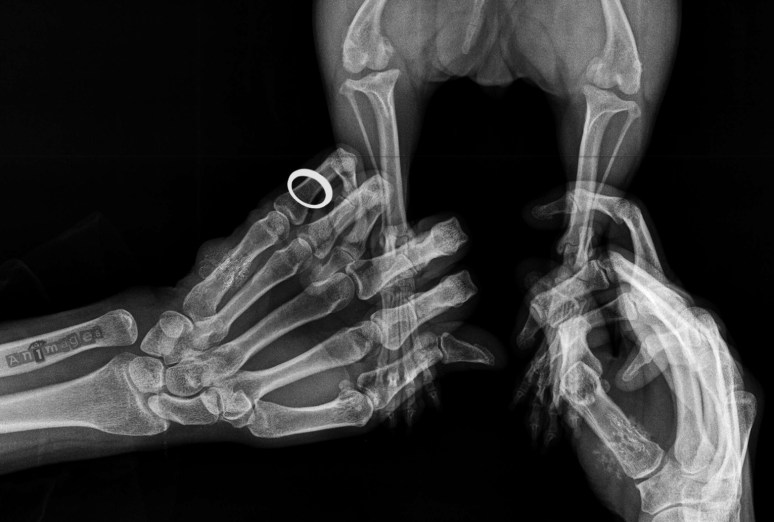

MISE EN GARDE: cette image n’est le fruit que de mon animagination. La vie de la personne au bout de ces doigts n’est pas en danger, du moins par pour le moment. 😉

Est-ce que l’humain a des lésions osseuses, type ostéosarcome sur le petit doigt gauche? 🙂

Non, te t’inquiète pas, ce fut l’oeuvre de Photoshop pour mettre un peu de poudre aux yeux… 😉